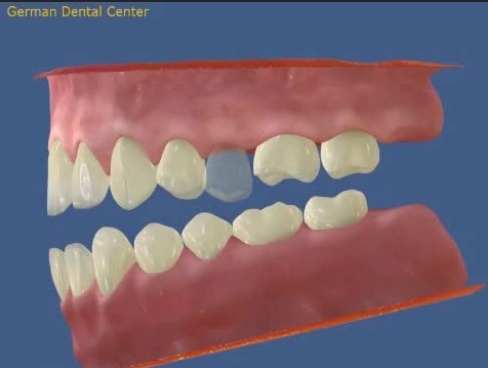

- Исправление прикуса

- Протезирование